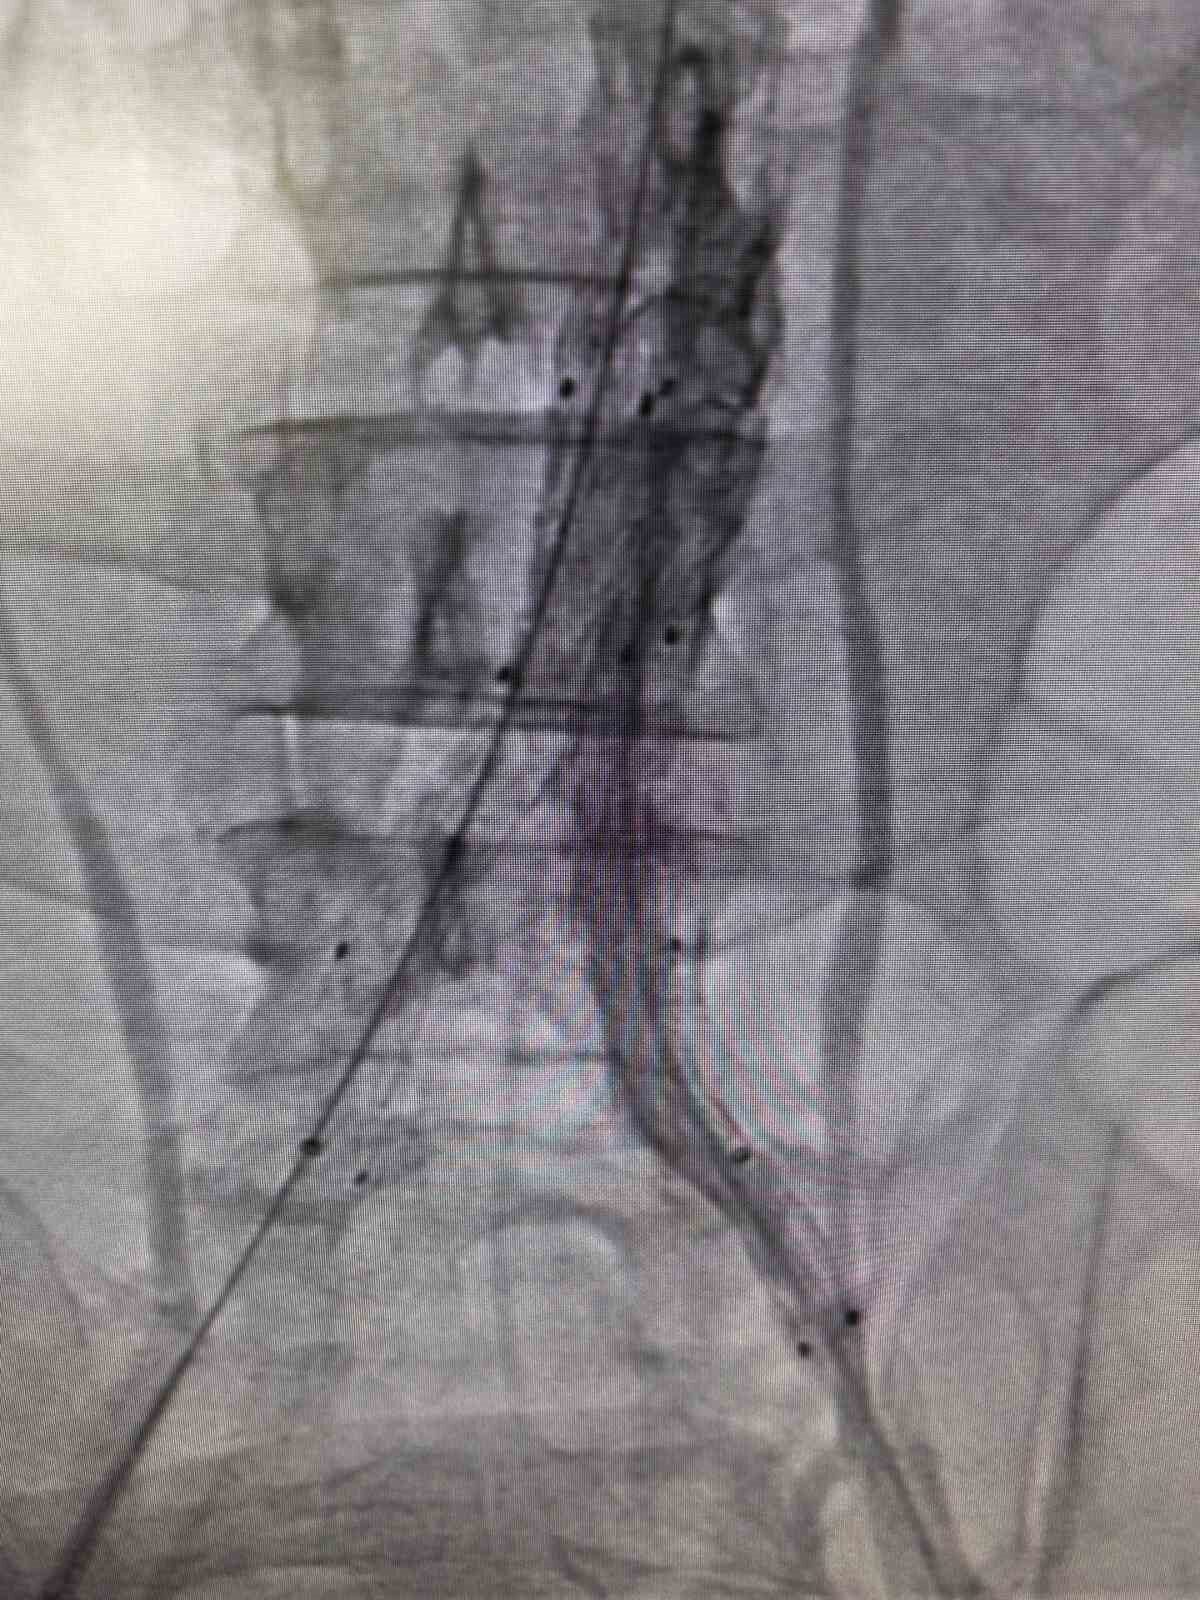

Bilecik’te, şiddetli sırt ve karın ağrısı şikayetiyle hastaneye başvuran bir bireyin yapılan kontrollerinde ana atardamarında hayati tehlike oluşturan ciddi bir yırtık tespit edildi. Yırtılan ana damarın içerisine özel bir stent yerleştirilerek damar içten onarıldı.

Bilecik Eğitim ve Araştırma Hastanesi’nde daha önce farklı sağlık kuruluşlarına başvuruda bulunan ve kesin bir tanı konulamayan hasta, acil serviste gerçekleştirilen detaylı tetkiklerle doğru tanıya ulaştırıldı. Şiddetli sırt ve karın ağrısı şikayetiyle hastaneye gelen 39 yaşındaki Mehmet D.’nin acil serviste çekilen ileri görüntüleme tetkiklerinde, kalpten çıkan ana damarın iç duvarında yırtık olduğu belirlendi. Hayati risk taşıyan bu durum nedeniyle hasta, kalp ve damar cerrahisi ekibi tarafından acil olarak değerlendirildi. Hasta, Kalp ve Damar Cerrahisi Uzmanı Op. Dr. Elmas Üreyen tarafından kapalı yöntemle tedavi edildi. Damar içinden girilerek gerçekleştirilen işlem sırasında, yırtılan ana damarın içine özel bir stent yerleştirildi ve damar içten onarıldı. Açık ameliyata gerek kalmadan yapılan bu uygulama sayesinde hasta kısa sürede rahatladı. Tedavi sonrası yakından izlenen hastanın ağrılarının tamamen geçtiği ve genel sağlık durumunun iyi olduğu gözlemlendi. Kontrollerinin sorunsuz geçmesi üzerine hasta sağlıklı bir şekilde taburcu edildi.